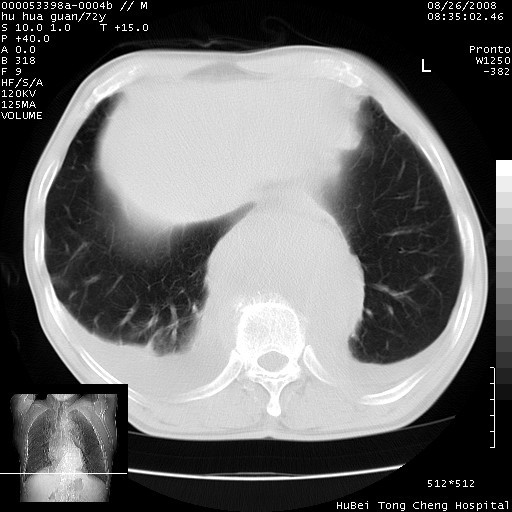

1、右上肺结节病变,肺泡癌不除外,请随诊;左下肺近后纵隔病变,考虑纵隔型肺癌侵犯大血管可能;

2、右下肺背段少许炎症,双侧胸腔积液,右下肺纤维索条。

降主动脉前移位,后纵隔占位

后纵隔占位,降主动脉前移位;双侧胸腔积液;应排外食管病变侵犯血管可能;